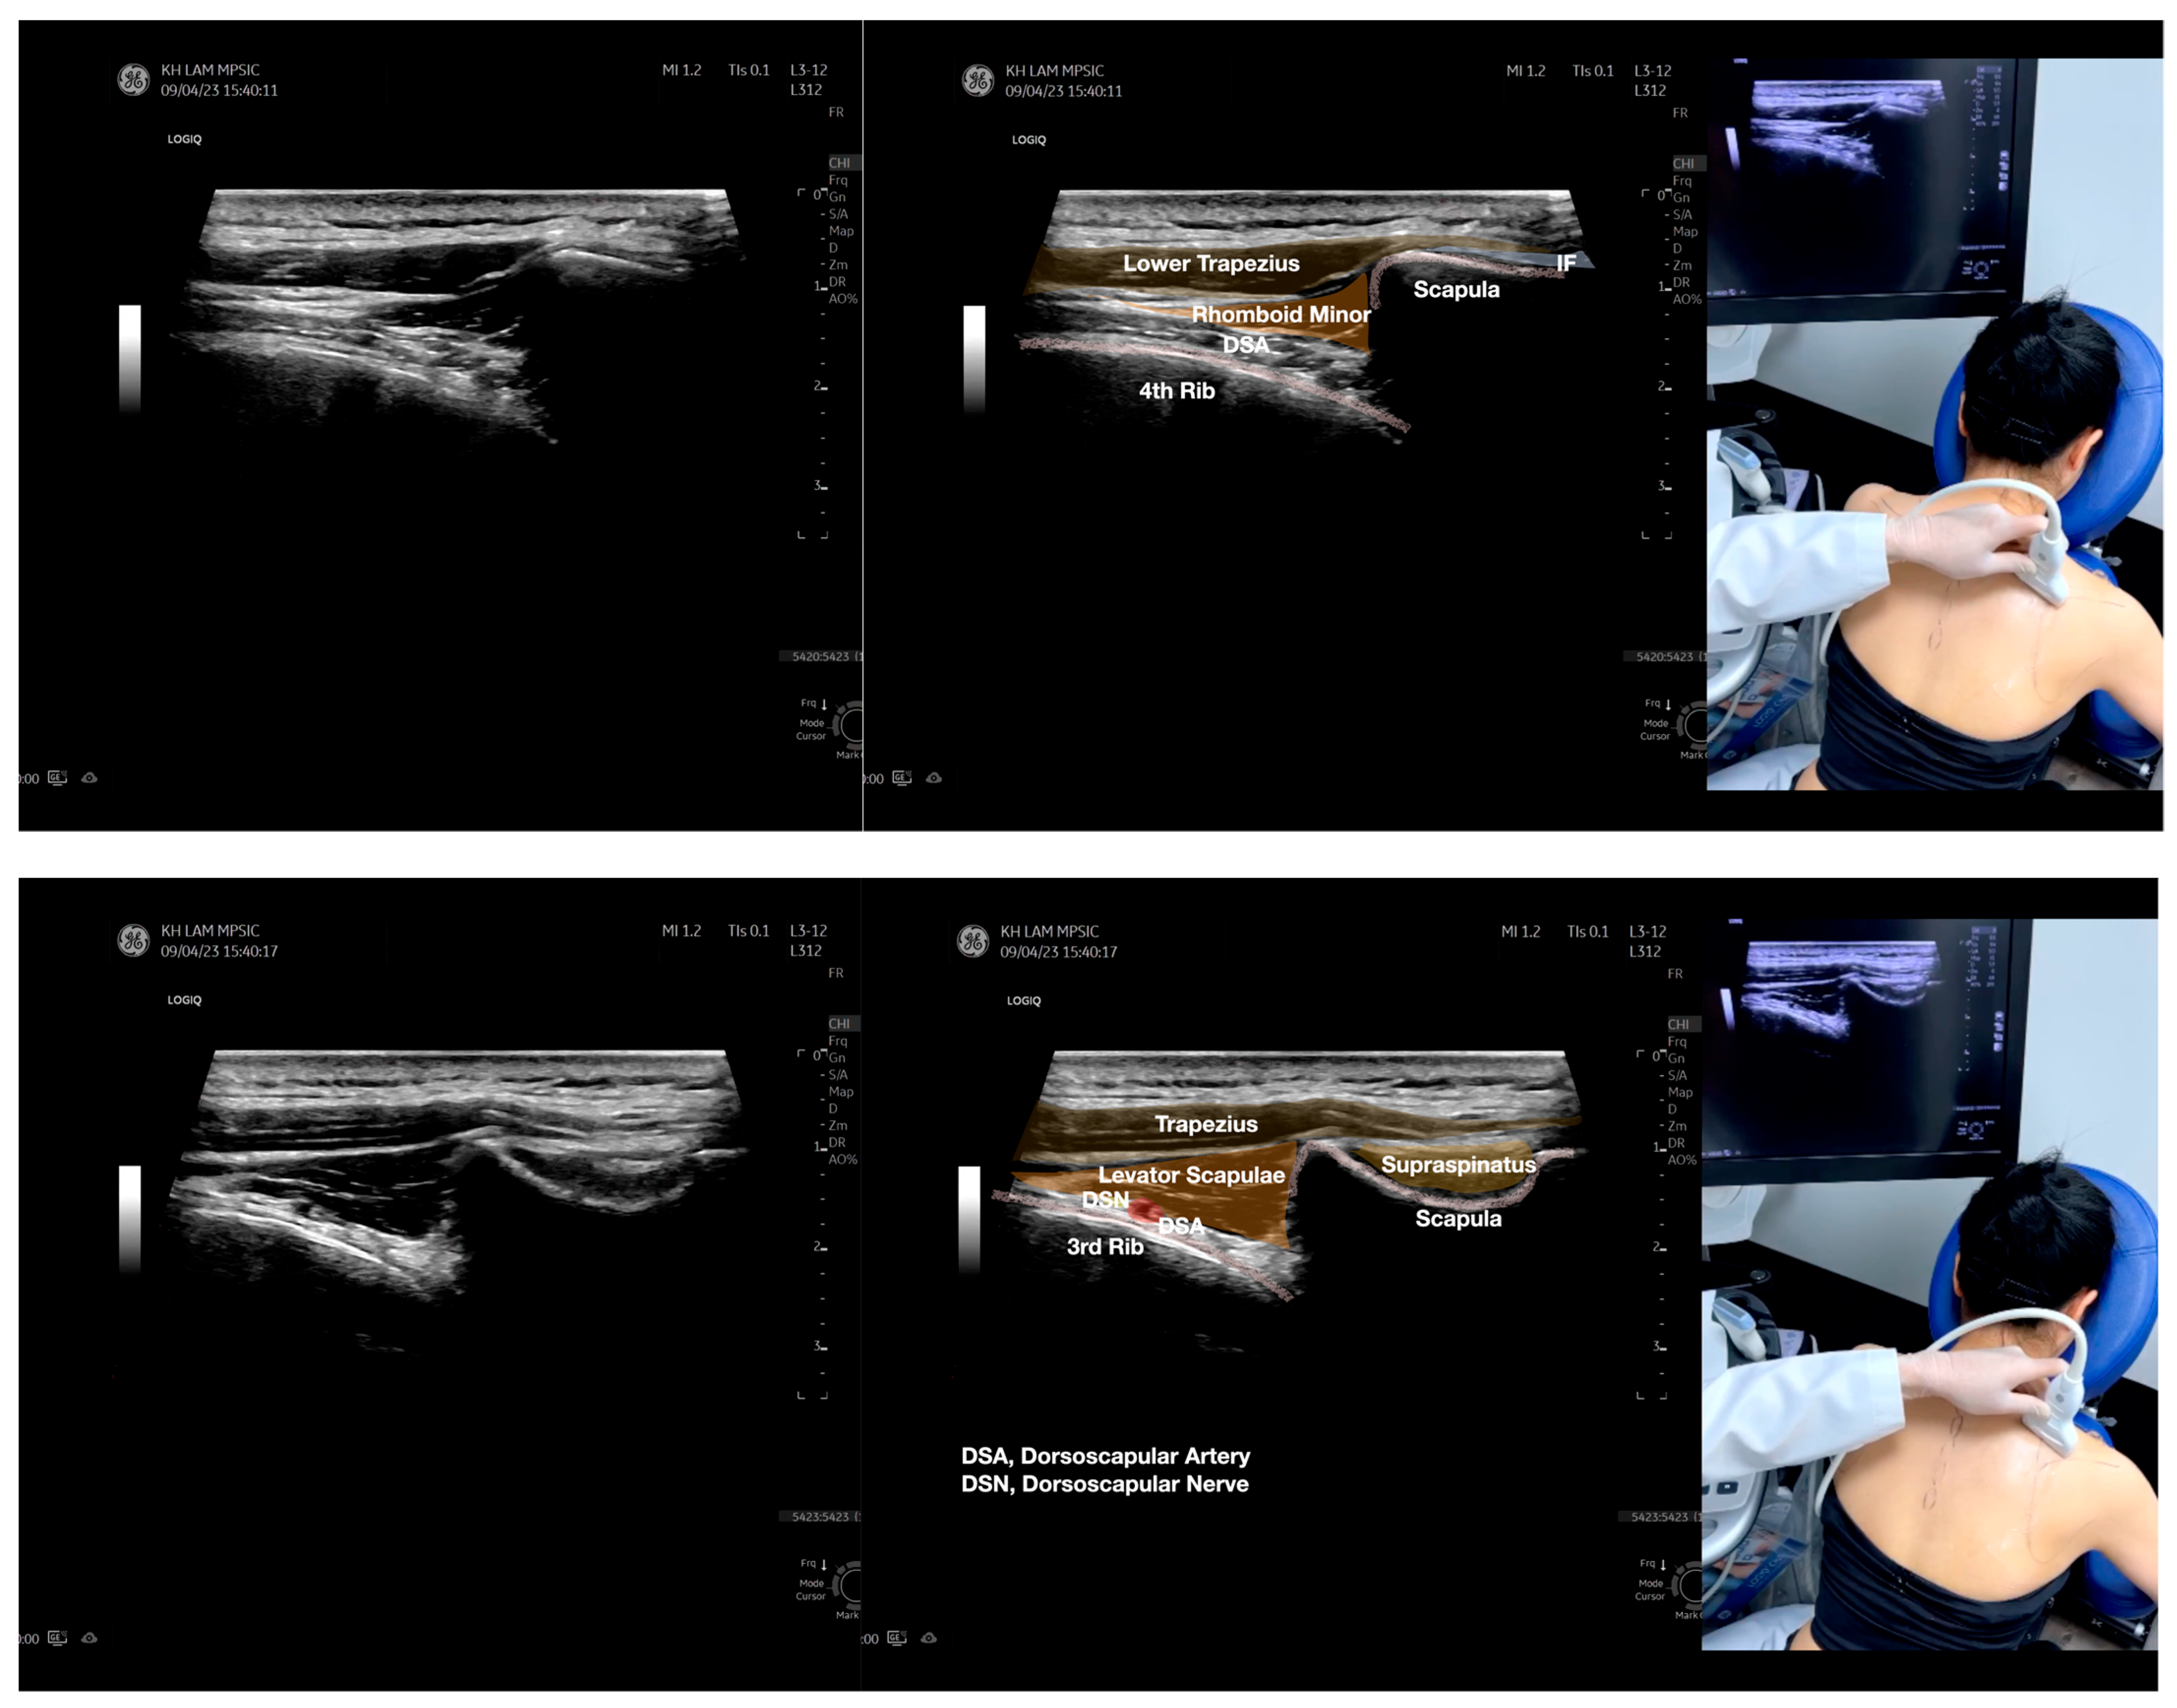

Figure 4.

Sonoanatomy of the medial edge of the scapula, its related muscles, and the infraspinatus fascia. The step-by-step scanning techniques of these structures illustrated in this figure have been shown in Video S8. Available online: https://www.dropbox.com/s/iaej3rxhl83kqt4/Figure%204.docx?dl=0 (accessed on 1 January 2023).